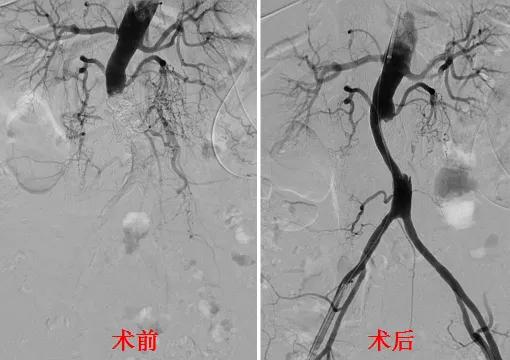

4月28日,宜宾市第二人民医院·四川大学华西医院宜宾医院(简称华西宜宾医院)血管外科为一位腹主动脉重度钙化闭塞患者顺利实施我市首例外周血管内冲击波技术开通血管,成功恢复其双下肢血流。

4月28日,血管外科副主任龚光带领熊义祥、刘盛智、刘彬医生,在介入室护理团队的大力配合下,为李阿姨顺利实施了腹主动脉造影、球囊扩张及支架植入术。手术后的李阿姨双下肢足背动脉搏动良好,双脚恢复了正常温度。

据龚光介绍,在高龄、糖尿病、高血压等慢性病患者中,动脉钙化的发病率显著增多,同时也增加了动脉介入手术的难度和风险。长期以来,我院血管外科致力于新技术、新方法的探索和实践,这次所采用的Shockwave外周血管内冲击波技术就是国际最新的解决血管钙化的新“*器武**”,它创新地将声波碎石术和血管成形术整合在同一球囊导管中,通过球囊内的电极触发脉冲产生相当于50atm的血管内冲击波,安全穿过动脉内膜,对钙化病变隔空敲打,让钙化断裂、血管恢复柔顺。同时,最大程度降低了夹层、栓塞和动脉破裂的风险,为钙化导致的严重肢体缺血、传统治疗不佳的患者带来了福音。